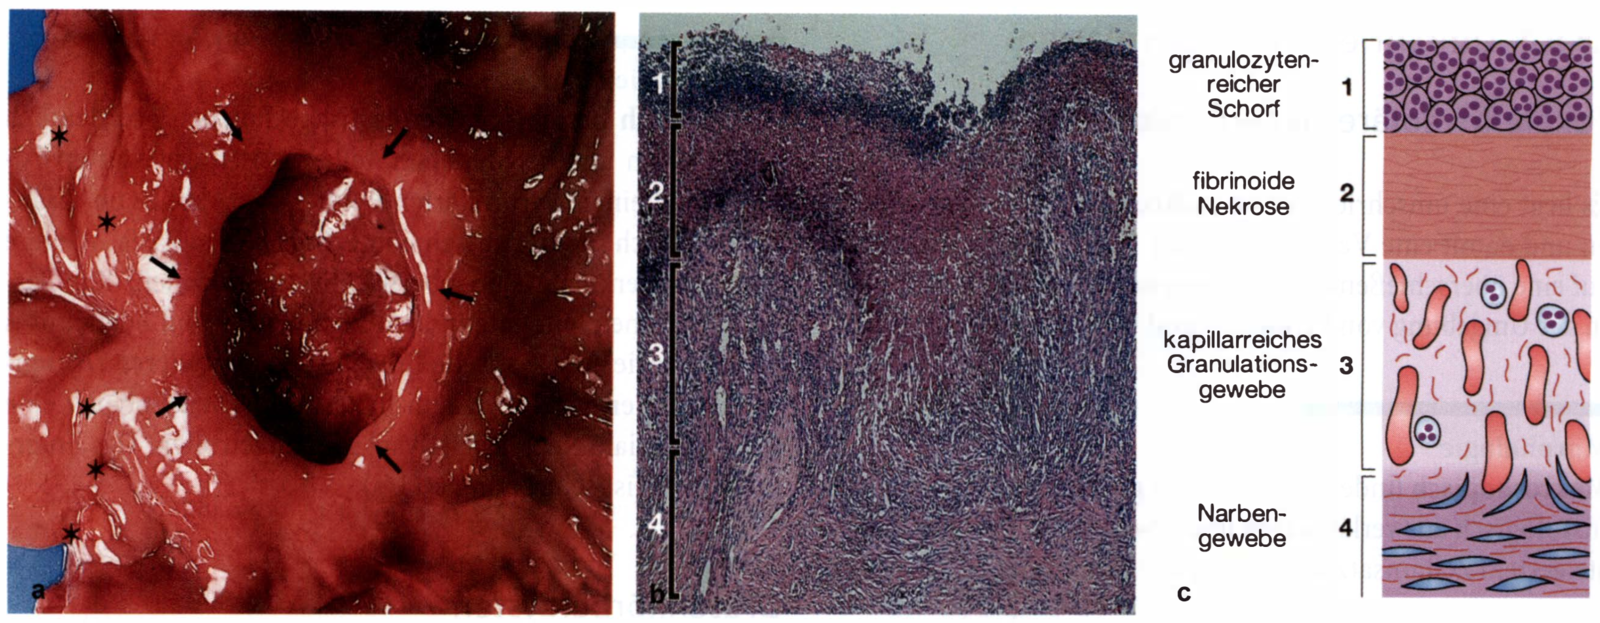

a Chronisches kallöses Magenulkus im präpylorischen Antrum (Pfeile). Pylorusring (Sternchen).

b Histologische Schichten des Ulkusgrunds.

1 = granulozytenreicher Schorf, 2 = fibrinoide Nekrose, 3 = Aufbau des Ulkusgrundgewebes.